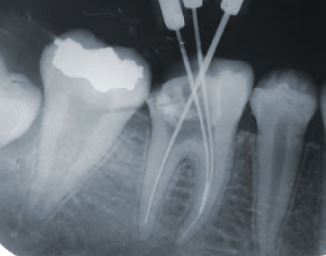

Gãy file và cách xử lý

• Xử trí